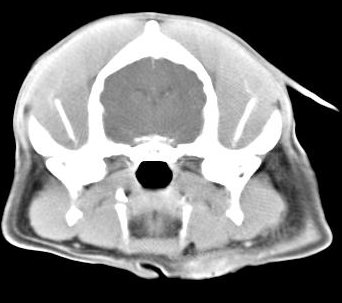

imágenes de TC en el perro | ||||||||||

ejemplo de imágenes de TC en el perro. Nótese la celulitis en la región parotídea izquierda | ||||||||||